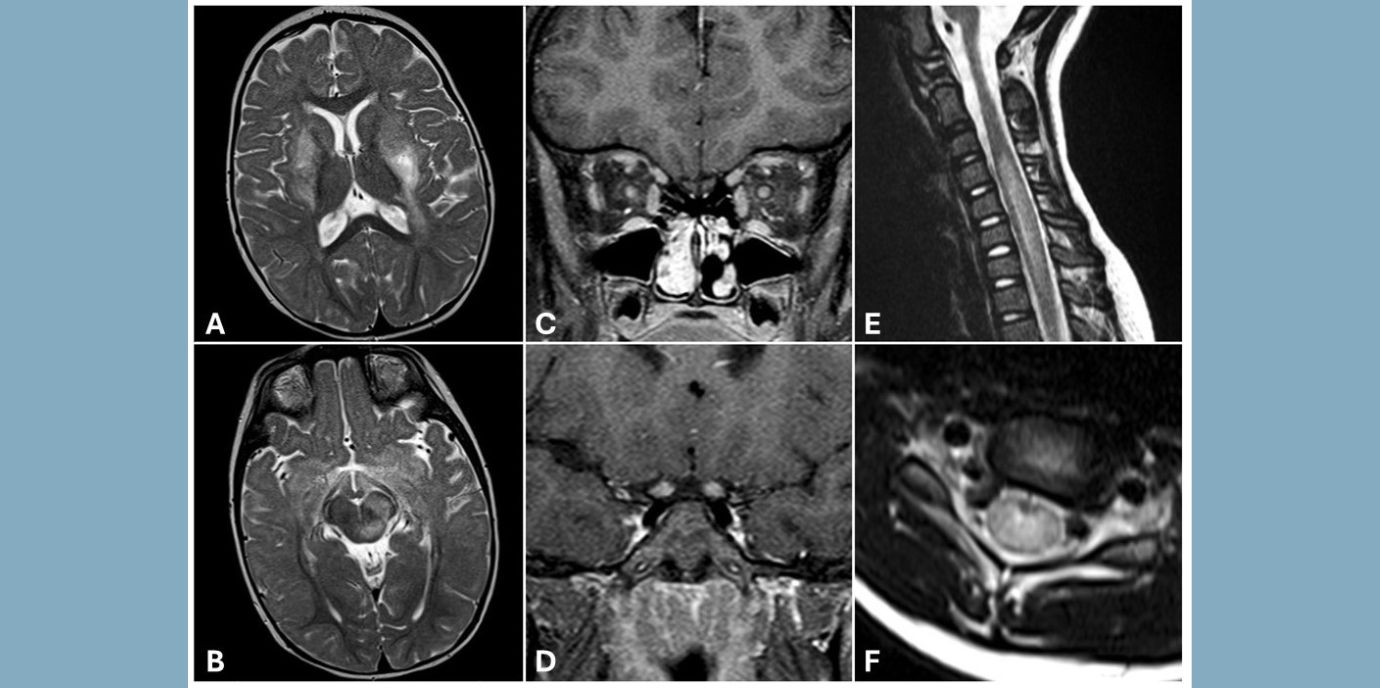

*MOGAD (Myelin Oligodendrocyte Glycoprotein Antibody-associated Disorders) sind entzündliche Erkrankungen des Zentralnervensystems mit unterschiedlichen Ausprägungen bzw. Subtypen. Bei Kindern dominiert meist ADEM (Acute Disseminated Encephalomyelitis), das von einer Enzephalopathie (Bewusstseinsstörung), häufig gepaart mit Koordinations- und motorischen Schwierigkeiten, Übelkeit und Kopfschmerzen charakterisiert ist, während Jugendliche und Erwachsene mehr von Optikusneuritis, einer Sehnerventzündung, betroffen sind. LETM (Transverse Myelitis bzw. Longitudinal Extensive Transverse Myelitis) trifft ebenso eher Jugendliche und Erwachsene und ist hauptsächlich durch Lähmungserscheinungen gekennzeichnet. Bis zur Hälfte aller MOGAD-Patient:innen sind von einem schubhaften Verlauf (multiphasisch) betroffen, während die übrigen an MOGAD Erkrankten eine einmalige, akute Krankheitsphase erleben.